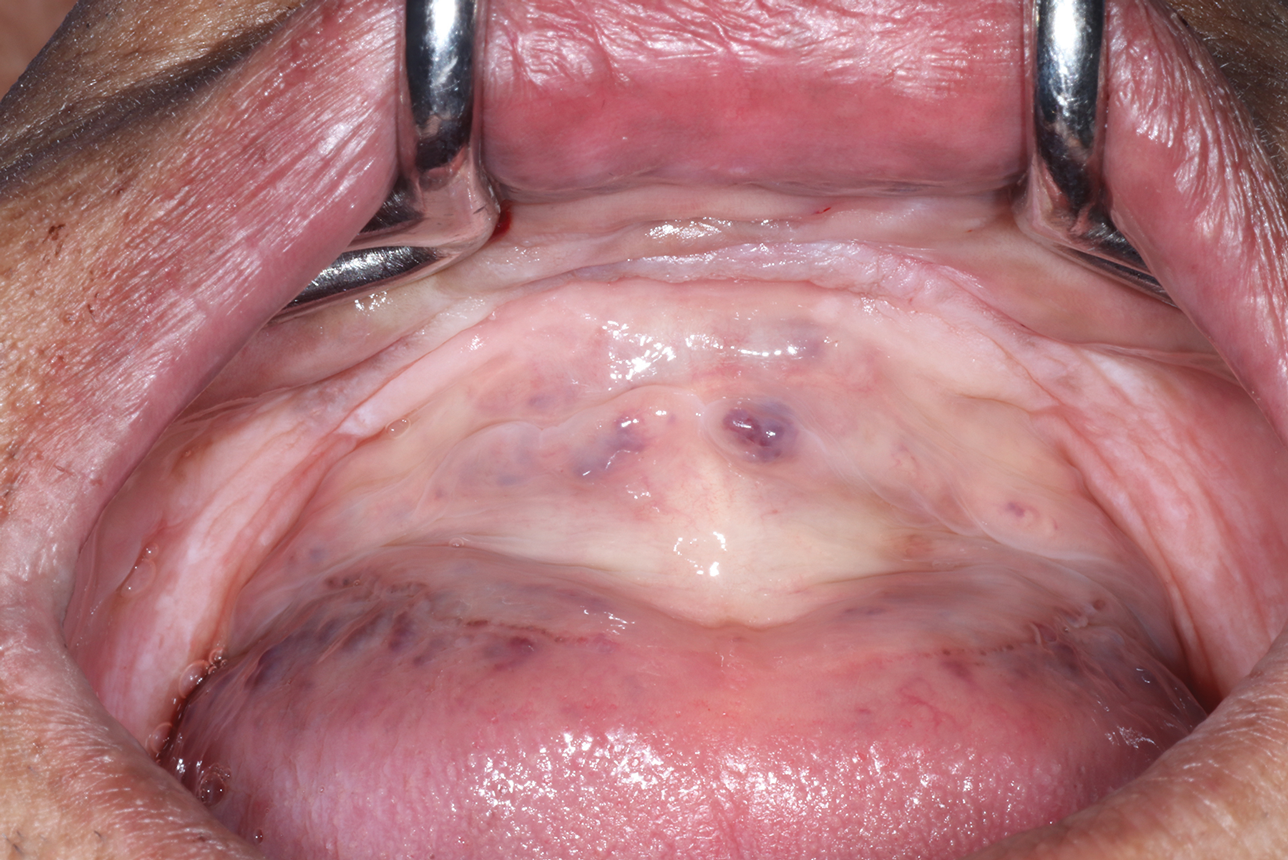

Beyond hard-to-reach areas and the presence of metal, other factors, such as patient movement and the presence of saliva or blood can compromise the integrity of digital impressions, leading to inaccuracies with the placement and fit of the prosthesis. The dynamic nature of the mucosa (Figure 2) presents an additional layer of complexity because intraoral scanners may struggle to capture its anatomy with the same level of detail and accuracy as harder tissue structures, such as the teeth or keratinized tissue.6 The efficient management of soft tissue is crucial to the long-term success of implant therapy, impacting both the stability of restorations and the esthetic outcome. Failure to accurately capture detailed information about the soft tissue can compromise the success of implant restorations, potentially resulting in issues such as poor gingival health, peri-implantitis, and undesirable prosthetic emergence profiles.7 Ensuring proper bedding of keratinized tissue during the surgical phase can significantly enhance the success of intraoral scanning and implant-supported restorations. Furthermore, employing innovative drilling protocols and placing implants into adequate cancellous bone (Figure 3 and Figure 4) can alleviate strain on the overlying cortical bone, which typically exhibits less vascularity, and consequently, reduce alveolar remodeling, ultimately preventing bone loss around the crestal neck of the implant.

(2.) The presence of mucosa in the absence of keratinized tissue results in soft-tissue mobility that makes intraoral scanning difficult.

Figure 2